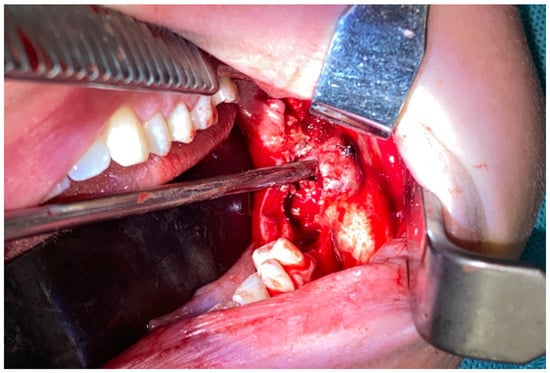

Figure 2. Initial diagnosis excluded any odontogenic cysts and tumors. Endocrine disorders were excluded; however, the value of PTH was in its upper range limits, which was atypical and not conclusive of a BT in PHP. The biopsy and evaluation of calcium–phosphate markers were not significant either. Because of lesion growth, the possibility of pathological fracture, secondary bone disfigurement, and perhaps a necessity in the future for a free-flap, the decision was made to undergo surgery while some of the patient’s own bone was still present. A possible option for a conservative approach was avoided to decrease the risk of any possible pathological mandibular fracture during this bone tumor progression. Because of the possibility of reducing the scope of surgery and maintaining a healthy lower mandibular bone border, it was possible to use an alternative approach different from the typical en-block resection with microsurgical reconstruction. Secondly, because of the patient’s young age and her expectancy for a good and less invasive outcome and avoidance of a facial scar, an intraoral approach was used. Because of the location, a superior-based mandibular body marginectomy with bone ostectomy, teeth removal (36–38), and resection of purple-like gum tumor with prophylactic stable bone osteosynthesis of the mandible was scheduled (two Medartis 2.0 titanium plates with seventeen screws 2.0 7/8 mm, Medartis, Basel, Switzerland). Intraorally, the entire polycystic lesion had a solid appearance without any mineralization or cystic appearance, but in both the radiological and clinical examination, the lesion had an expansile behavior. The lower inferior alveolar nerve was displaced within the tumor’s inferior aspect and was not untacked during surgery. The entire bone defect was filled with allogenic bone grafts (20 cm3 of bone) from the local bio-bank and additional bone marrow aspirate concentrate (BMAC) from the iliac crest, with blood mixed together. Three collagen membranes (Matrix Flex, Athena Marketing, Vadodara, Gujarat, India) were placed on the lingual aspect of the bone and sutured with 4.0 Prolene sutures (Prolene—B.Braun, Melsungen, Germany) to the flaps to ensure more stability to the allogenic bone. Four additional IMF screws (intramaxillary fixation, Medartis, Basel, Switzerland) were applied to avoid any secondary trauma.